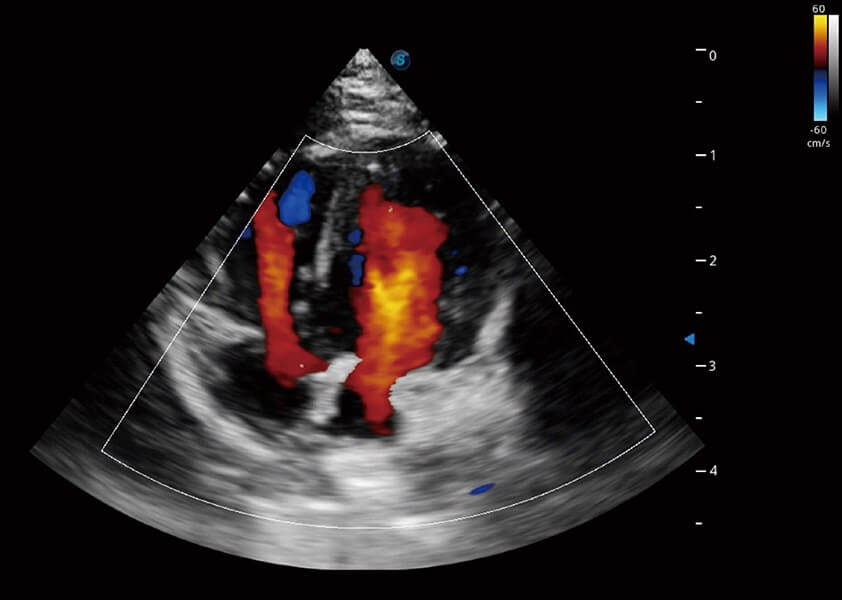

ProPet 60 作为一款高端台式动物超声设备,为动物医生的日常诊断提供了一系列贴合动物临床需求、解决临床实际问题的高级成像功能。凭借全系列高清探头,满足医生对腹部、心脏、生殖、浅表、肌骨等成像的所有需求,切实帮助您提升检查效率,提高诊断信心。

兽用彩色多普勒超声诊断系统

动物是人类最亲密的朋友和最值得信赖的伙伴。美狮贵宾会官网也一直致力于探索动物专用的超声影像解决方案。 全新推出的ProPet系列,是美狮贵宾会官网在动物超声影像智能化、专业化、精准化的一次跨越式革新。动物不能用言语来表述自己的不适,通过超声影像,ProPet系列搭建了动物医生与不同物种沟通的“桥梁”,为动物医生注入了“治愈之力”。